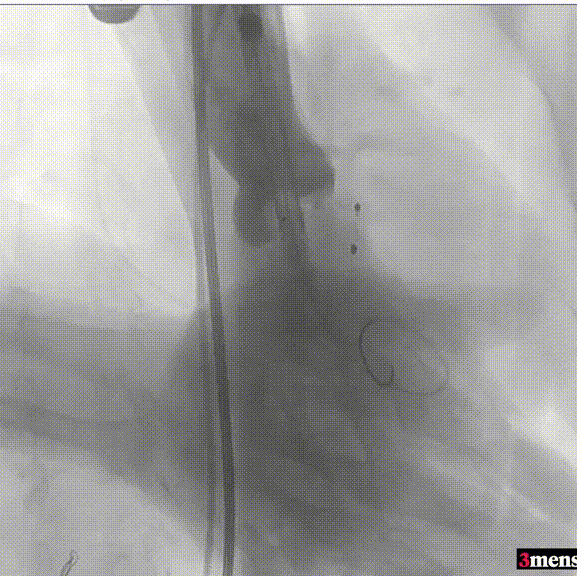

手术过程回顾:

患者全麻后,右侧股动脉建立主入路,主动脉根部造影显示主动脉瓣明显钙化。心室内轻微反流,主动脉及心脏情况整体较为稳定。直头导丝跨瓣后,在超硬导丝支撑下,瓣膜输送系统顺利跨瓣。在180次/分快速心室起搏下,确定降压至50mmHg后选择18mm球囊进行预扩张。在球囊扩张后,该患者血压未见升高,随即进行胸外按压,同时根据术前评估及球囊预扩情况,选取直径23mm瓣膜果断快速进行瓣膜定位并释放。瓣膜释放后患者心律和血压趋于平稳。

瓣膜释放至工作位

瓣膜脱钩

造影查看瓣膜形态

球囊后扩

最终造影

瓣膜释放后,超声提示患者存在一定的跨瓣压差和反流,通过球囊后扩,患者跨瓣压差即刻显著下降,反流量轻微。术后患者心功能持续得到改善,效果良好,此次手术取得圆满成功。